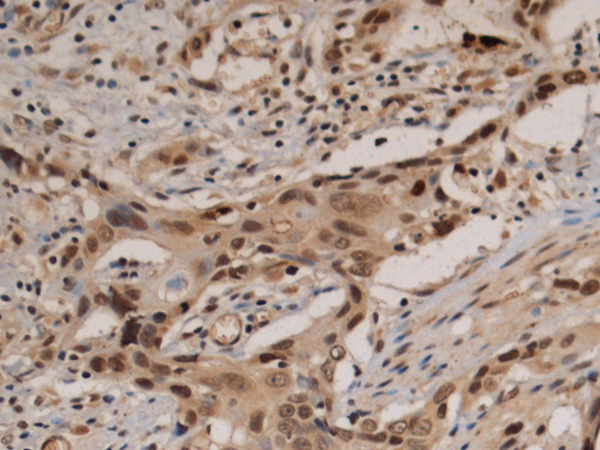

分类: 科研抗体货号: P10442别名: IF; GIF; INF; IFMH; TCN3应用: IHC反应种属: Human, Mouse, Rat

分类: 科研抗体货号: P10438别名: AP2REP; AP-2rep; HSPC122应用: IHC反应种属: Human, Mouse